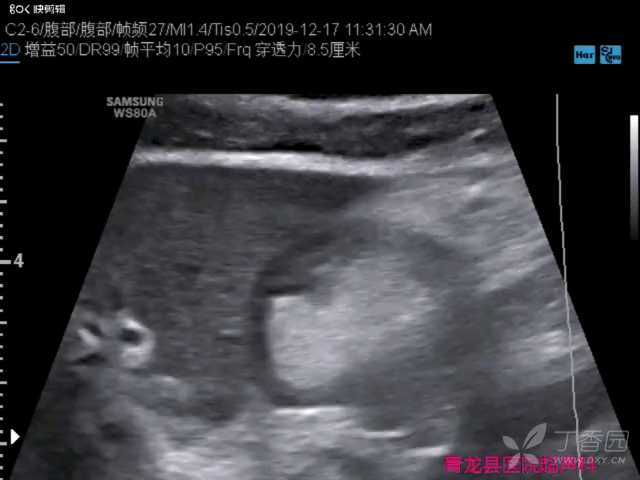

胃窦部溃疡超声表现一例

54岁男性,因腹部不适,腹部彩超检查过程中无意间发现:胃窦前壁可见一固定强回声,考虑溃疡,胃镜证实了我们的诊断。

1.胃溃疡声像图表现(1)病变处胃壁呈局限性增厚,回声偏低,其厚度常小于15mm,范围小于50mm。其中央黏膜面完整性破坏,呈现大小不一、深浅不等的缺陷性黏膜凹陷,其矢状切面呈月牙形、陷坑状;冠状切面呈圆环形或靶环形。病变处黏膜凹陷口形态规整、光滑柔软;一般口大底小,底部平坦;表面可附有强回声斑点、斑块回声,不随胃蠕动而消失。